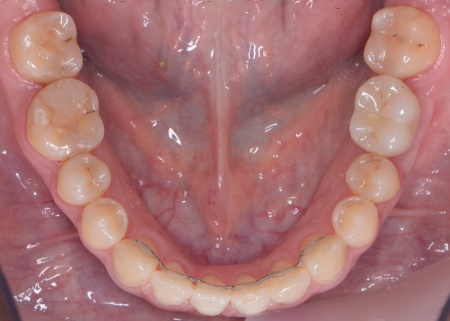

インプラント手術後は矯正治療の仕上げを行い、装置を外しています。

歯並びが後戻りしないよう保定装置を装着していただき、その後、インプラントの上部に人工の歯を取り付けました。

治療終了後、下前歯の間に見られる三角形のすき間(ブラックトライアングル)が気になるとのご相談がありました。

そこで、歯の表面に白いプラスチック樹脂を直接盛り付けて形を整えるダイレクトボンディングを行い、すき間が目立ちにくいよう調整して、治療を終了しました。